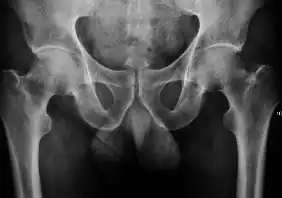

Projectional radiography ("X-ray") is currently useful not only in older people in whom osteoarthritis of the hip is suspected but also in younger people without osteoarthritis, who are being evaluated for femoroacetabular impingement (FAI) or hip dysplasia.[1]

Plain radiography allows us to categorize the hip as normal or dysplastic or with impingement signs (pincer, cam, or a combination of both). Besides these, pathologic processes like osteoarthritis, inflammatory diseases, infection, or tumors can also be identified (Figure 1).[1]

Figure 1.

Osteoarthritis

In adults, one of the main indications for radiographs is the detection of osteoarthritic changes (Figure 1(e)). Nevertheless, radiographs usually detect advanced osteoarthritis that can be graded according to the Tönnis classifications. The grading system ranges from 0 to 3, where 0 shows no sign of osteoarthritis. Intermediate grade 1 shows mild sclerosis of the head and acetabulum, slight joint space narrowing, and marginal osteophyte lipping. Grade 2 presents with small cysts in the femoral head or acetabulum, moderate joint space narrowing, and moderate loss of sphericity of the femoral head. Grade 3 is the severest form of osteoarthritis, which manifests as severe narrowing of the joint space, large subchondral cyst with productive bone changes that may lead to deformity of the bone components of the joint, while secondary osteoarthritis due to calcium pyrophosphate deposition can be diagnosed when calcification of hyaline cartilage and fibrocartilage is detected.[1]

There are other pathological conditions that can affect the hip joint and radiographs help to make the appropriate diagnosis. Acute bacterial septic arthritis can be diagnosed by radiographs when a fast regional osteoporosis and destructive monoarticular process develops (Figure 1(f)). In case of tuberculous or brucella arthritis it is manifested as a slow progressive process, and diagnosis may be delayed.[1]